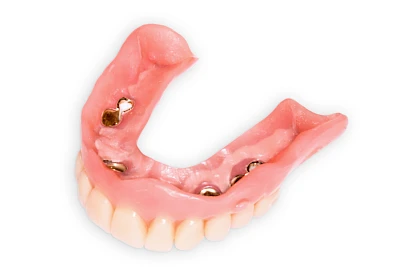

Implantate: Prothesen

Bei herausnehmbaren Prothesen werden Implantate eingesetzt, um den Halt und den Tragekomfort der Prothesen zu verbessern. Dazu kommen verschiedene Verbindungselemente zum Einsatz:

- Teleskope

- Kugelköpfe

- Tellerförmige Lokatoren

- Stege

- Magnete (selten)

Neben rein implantat-getragenen zahnärztlichen Versorgungen werden bei herausnehmbaren Prothesen Implantate auch in Sinne einer "strategischen Pfeilervermehrung" ergänzend zu eigenen Zähnen zur Verankerung eines Zahnersatzes genutzt.

Varianten zur Verankerung von abnehmbarem Zahnersatz auf Implantaten